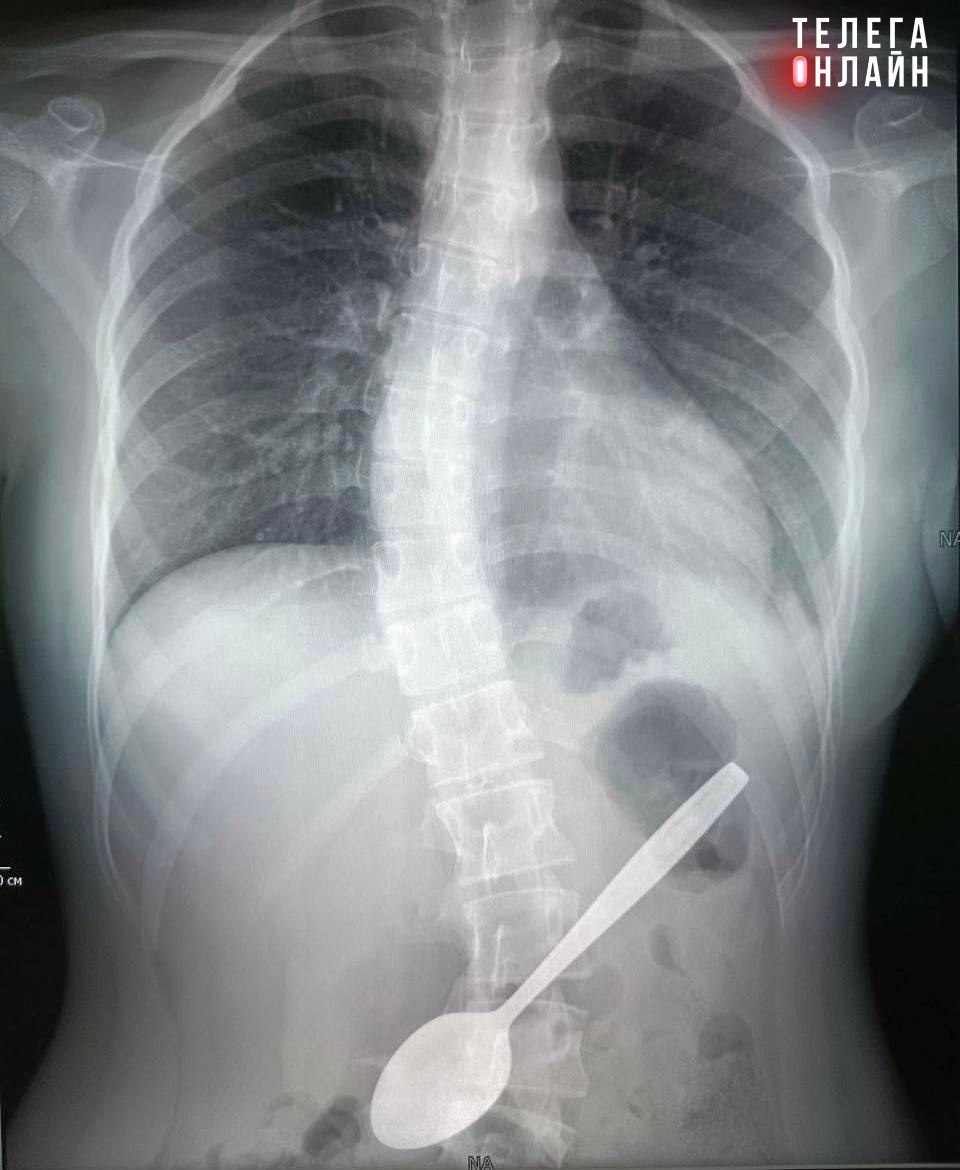

В Подмосковье врачи извлекли из желудка школьницы 15-сантиметровую ложку.

Когда за первые майские выходные разогнался аппетит и внезапно наступает трехдневная рабочая неделя.